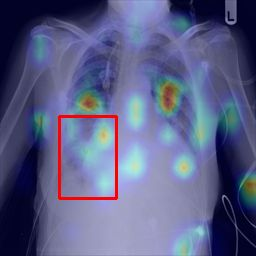

Deployments of artificial intelligence in medical diagnostics mandate not just accuracy and efficacy but also trust, emphasizing the need for explainability in machine decisions. The recent trend in automated medical image diagnostics leans towards the deployment of Transformer-based architectures, credited to their impressive capabilities. Since the self-attention feature of transformers contributes towards identifying crucial regions during the classification process, they enhance the trustability of the methods. However, the complex intricacies of these attention mechanisms may fall short of effectively pinpointing the regions of interest directly influencing AI decisions. Our research endeavors to innovate a unique attention block that underscores the correlation between 'regions' rather than 'pixels'. To address this challenge, we introduce an innovative system grounded in prototype learning, featuring an advanced self-attention mechanism that goes beyond conventional ad-hoc visual explanation techniques by offering comprehensible visual insights. A combined quantitative and qualitative methodological approach was used to demonstrate the effectiveness of the proposed method on the large-scale NIH chest X-ray dataset. Experimental results showed that our proposed method offers a promising direction for explainability, which can lead to the development of more trustable systems, which can facilitate easier and rapid adoption of such technology into routine clinics. The code is available at www.github.com/NUBagcilab/r2r_proto.